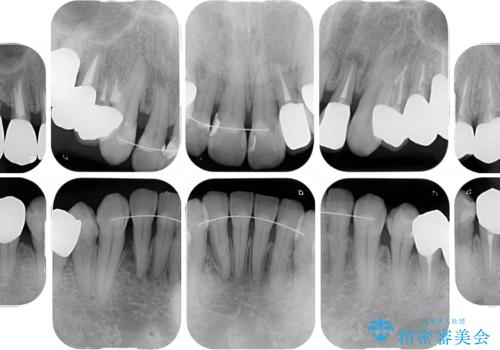

全体的に中等度の歯周病と診断されたため、歯周外科処置やインプラントによる咬合回復から進めて行き、矯正治療による歯列改善を行った後にオールセラミッククラウンにて補綴することとしました。

歯槽骨の再生治療を行ったため、外科処置後の静置期間がながくなり、4年弱の治療期間となりました。